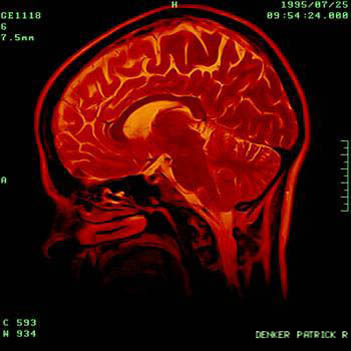

The researchers scanned the brains of 103 healthy people between the ages of 5 and 32 and found that the wiring in the frontal lobes of the young adult participants was still developing. The frontal lobe is responsible for complex cognitive tasks such as inhibition, high-level functioning and attention, according to a University of Alberta press release.

“This is the first long-range study, using a type of imaging that looks at brain wiring, to show that in the white matter there are still structural changes happening during young adulthood,” said researcher Catherine Lebel. “The white matter is the wiring of the brain; it connects different regions to facilitate cognitive abilities. So the connections are strengthening as we age in young adulthood.”

The researchers also found reduced white matter in the brains of some of the participants, which, they said, is associated with the degradation of the brain. Researcher Christian Beaulieu said this study could yield future studies on the correlation of brain structure and mental health problems, which begin in adolescence.